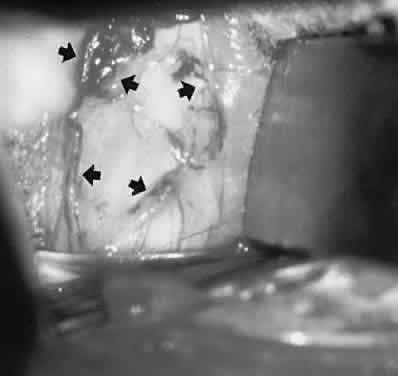

Orbital pseudotumor and the Tolosa-Hunt syndrome are likely the same process, varying only in that the idiopathic inflammation involves predominantly the orbit in the former and predominantly the superior orbital fissure and/or the anterior cavernous sinus in the latter. Idiopathic inflammation is a diagnosis of exclusion, made only in a fairly circumscribed clinical context, and when other pathologic processes have been ruled out. In this regard, contrast-enhanced CT scan or MRI shows diffuse infiltration or focal lesions, usually with notable enhancement of the posterior wall of the globe (Fig. 15). With proper orbital imaging and ultrasonographic assessment as diagnostic procedures, tissue biopsy is rarely necessary, and the response to systemic corticosteroid administration is usually dramatic, if not diagnostic (see also Volume 2, Chapter 12).

Fig. 15. Contrast-enhanced computed tomography (CT) scan in patient with painful ophthalmoplegia, lid swelling, and proptosis. In unilateral case, note enhancing envelope of thickened sclera (arrows) on coronal (A) and axial (B) sections of left globe. C. Bilateral orbital pseudotumor shows shaggy infiltration of orbital soft tissues (arrows) surrounding globes and optic nerves.